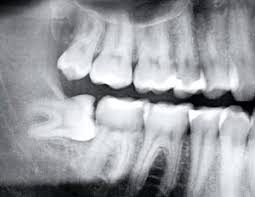

매복 사랑니란 위 엑스레이 사진처럼 잇몸 밖으로 완전히 나오지 못하고 묻혀있는 사랑니를 말합니다 (출처: https://mosmanvillagedentistry.com.au/)

매복사랑니란

사랑니가 정상적으로 올라오지 못하고

잇몸이나 뼈 속에 부분적으로 묻혀 있는 상태를 말합니다.